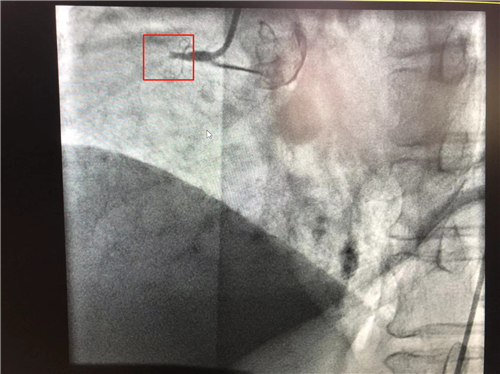

時(shí)間就是心肌,時(shí)間就是生命。導(dǎo)管室內(nèi),心血管內(nèi)科副主任徐先進(jìn)、主任助理農(nóng)彥林已然待命,病人一到,團(tuán)隊(duì)立即為其行深靜脈穿刺泵入血管活性藥物等,情況緩解后,行多體位冠狀動(dòng)脈造影,確認(rèn)RCA(右冠狀動(dòng)脈)近端完全閉塞。經(jīng)家屬同意,在汪念東院長(zhǎng)的指導(dǎo)下,徐先進(jìn)、農(nóng)彥林、張星為患者行經(jīng)皮冠狀動(dòng)脈球囊擴(kuò)張成形術(shù)+經(jīng)外周靜脈穿刺中心靜脈置管術(shù)。術(shù)中,張奶奶再次出現(xiàn)室顫,心血管內(nèi)科團(tuán)隊(duì)臨危不亂,立即予以300焦電除顫搶救,患者竇性心律恢復(fù)。隨后,球囊擴(kuò)張為其置入心臟支架,復(fù)查造影顯示血管恢復(fù)暢通,無明顯夾層,殘余狹窄不到10%。術(shù)后,張奶奶血壓偏低,轉(zhuǎn)入ICU無創(chuàng)呼吸監(jiān)護(hù),2天后轉(zhuǎn)回心血管內(nèi)科護(hù)理。

術(shù)前:右冠近端閉塞